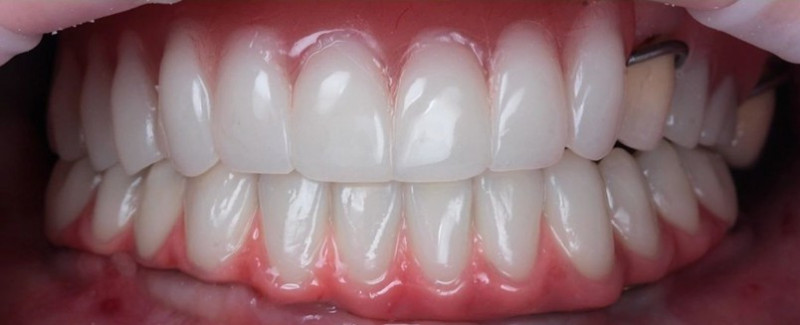

На странице представлено портфолио стоматологий Новосибирска с фото работ до и после имплантации зубов. Мы собрали разные клинические случаи: одиночные импланты, восстановление нескольких зубов и полная реконструкция зубного ряда. Здесь вы можете видеть, как выглядят восстановленные зубы, меняется форма улыбки после процедуры. Изучите результаты до и после имплантации зубов, чтобы оценить качество работы врачей и выбрать стоматологию в Новосибирске, которая поможет вернуть функциональность и эстетику вашей улыбке.

Жалобы: на отсутствие зубов, неудовлетворительную эстетику зубных рядов, невозможность жевать, подвижность зубов. Что сделано: удаление зубов на в/ч и н/ч, установка имплантатов Bredent Sky (верхняя челюсть 6 импл, нижняя 4 импл) и одномоментное протезирование акриловыми протезами с опорой на имплантаты по протоколу Fast & Fixed (зубы за один день). Через 10 месяцев проведена работа по замене протезов на постоянные металлокерамические. Что получил пациент: красивую улыбку, возможность нормально питаться с первого дня после операции.

Жалобы: на отсутствие зубов, неудовлетворительную эстетику зубных рядов, невозможность жевать, снижение высоты прикуса. Что сделано: удаление зубов на в/ч и н/ч, установка имплантатов Bredent Sky и одномоментное протезирование акриловыми протезами с опорой на имплантаты по протоколу Fast & Fixed (зубы за один день). Через 8 месяцев проведена работа по замене протезов на постоянные металлокерамические. Что получил пациент: красивые и ровные зубные ряды, возможность нормально питаться с первого дня после операции, поднята высота прикуса, теперь не стесняется улыбаться.